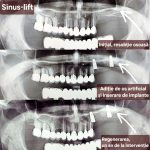

Augmentarea osoasă (adiția de os) este o procedură stomatologică ce restabilește volumul osos maxilar/mandibular resorbit, necesară pentru fixarea stabilă a implanturilor dentare. Aceasta utilizează materiale autogene (de la pacient), sintetice sau osoase, deservind ca bază solidă pentru reconstrucția osoasă, adesea însoțită de o membrană de protecție.

Este necesară atunci când osul este prea subțire, scurt sau deteriorat care nu poate susține un implant dentar, frecvent după extracții dentare, boala parodontală, atrofie osoasă după pierderea dinților, sau atunci când sinusurile maxilare pot fi situate prea aproape de acesta ceea ce împiedică inserarea implantului dentar

Cea mai răspândită intervenție de augmentare osoasă în stomatologie este operația de sinus lift (ridicarea sinusului) – o procedură chirurgicală de adiție osoasă realizată la maxilarul superior pentru a crește volumul osos necesar inserării implanturilor dentare. Prin ridicarea membranei sinusale și introducerea unui material de grefare, se creează o bază solidă, fiind necesară când sinusurile sunt prea coborâte sau osul este prea subțire. Scopul acestei proceduri este crearea unui suport stabil pentru implanturi dentare în zona laterală superioară (molari/premolari). Procedura de adiție osoasă se efectuează sub anestezie locală. Vindecarea durează de obicei între 4 și 6 luni.